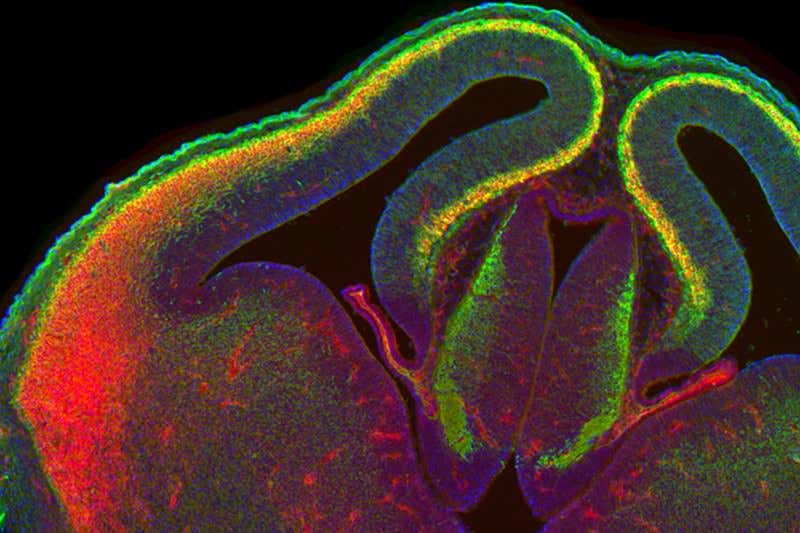

(Image: Andreas Zembrzycki/Salk Institute)

It’s easy for a mouse to change its mind, at least when it’s very young. Neurons normally responsible for interpreting sound or touch, for example, can swap senses while they are maturing, taking on vision instead. In the brain image above, neurons shown in yellow have been rewired, changing the type of sensory input they are able to process.

Andreas Zembrzycki from the Salk Institute for Biological Studies in La Jolla, California, and his colleagues have shown that a protein called Lhx2, which can change the function of sensory neurons by switching genes on or off, is the key. Previously, it was thought to alter neurons only before birth.